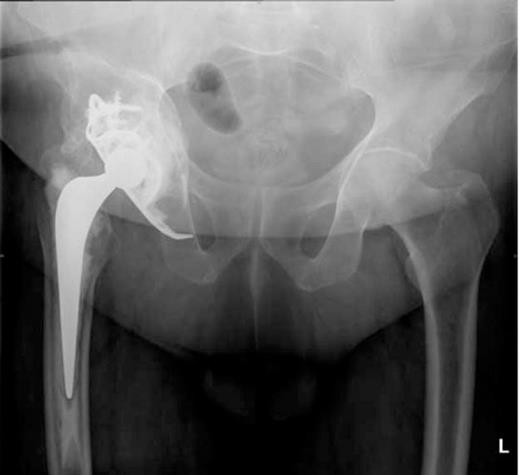

He was admitted to the High Dependency Unit for post operative recovery where he spent 6 days. On return to the elective ward, he made an uneventful recovery and required anticoagulation with warfarin for six months to protect the IVC filter. The most recent radiograph of his pelvis (Figure 4) showed excellent incorporation of the bone graft.